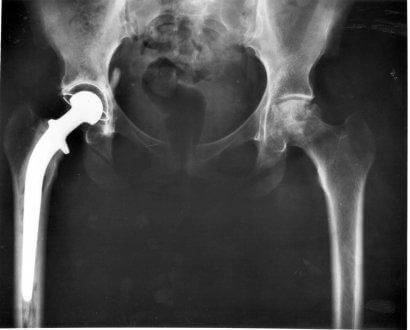

Hansen tyypin I välilevytyrän leikkaus

Vaikka emme voikaan sanoa, että leikkaus olisi hyvä ratkaisu koirallesi, voimme kuitenkin antaa neuvoja päätöksen tekemiseen. Ensinnäkin on tärkeää ymmärtää, että kaikki leikkaukset eivät ole tehokkaita. Onnistumisen todennäköisyys on kuitenkin melko suuri, jos sairaus havaitaan ajoissa.

Kaikki riippuu siitä, mitä neurologi sanoo – leikkaus voidaan välttää, jos eläin pystyy edelleen kävelemään tyrästään huolimatta, ja jos asiantuntijan mukaan on kyseessä ainoastaan välilevyn työntyminen ulos. Tällöin koiran tulee käydä läpi kuuden viikon hoito, johon kuuluu ehdotonta lepoa, kortikoidilääkitys sekä vatsan suojaus.

Tulee muistaa, että jos leikkaus valitaan, eläin tarvitsee pari viikkoa täyttä lepoa. Mahdollisuudet takajalkojen heikkouden korjaantumisesta ovat suuret.